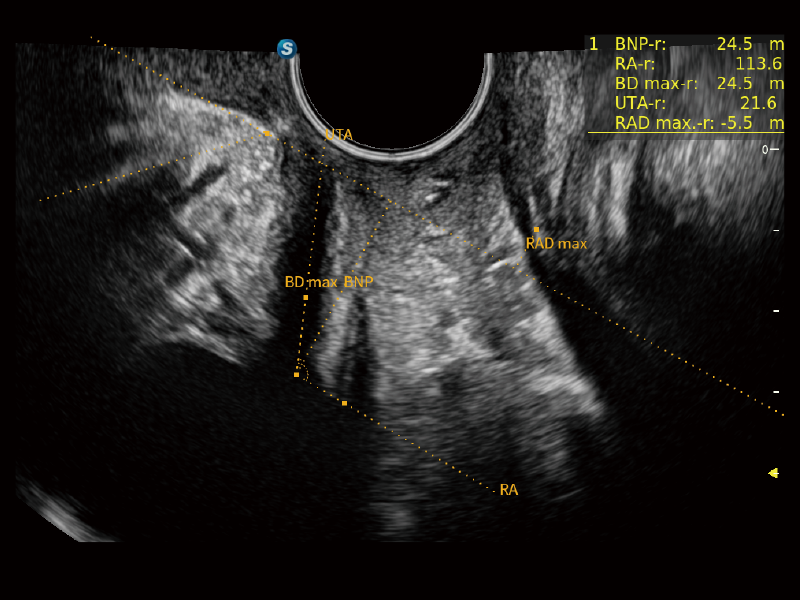

Exquisite Image Clarity & Hemodynamics

Image quality always lies at the core of definitive clinical outcomes. The P80 Elite introduces evolutional transducers with excellent 2D image clarity and color sensitivity for more confident assessment in anatomy and pathology.

Premium Transducer Solution

P80 Elite provides a series of advanced specialized transducers to empower ultrasound professionals for more confident and efficient assessment of anatomy to fullfill women’s healthcare needs.

Comprehensive Solutions For Women’s Health

Starting from a foundation of “Caring for Women”, the P80 Elite offers a comprehensive solution tailored to women’s healthcare needs, including gynecology, reproductive health examinations, prenatal screening, and postpartum rehabilitation. Our commitment extends beyond women’s health, encompassing the growth and care of the next generation.

Auto NT with HD-Zoom